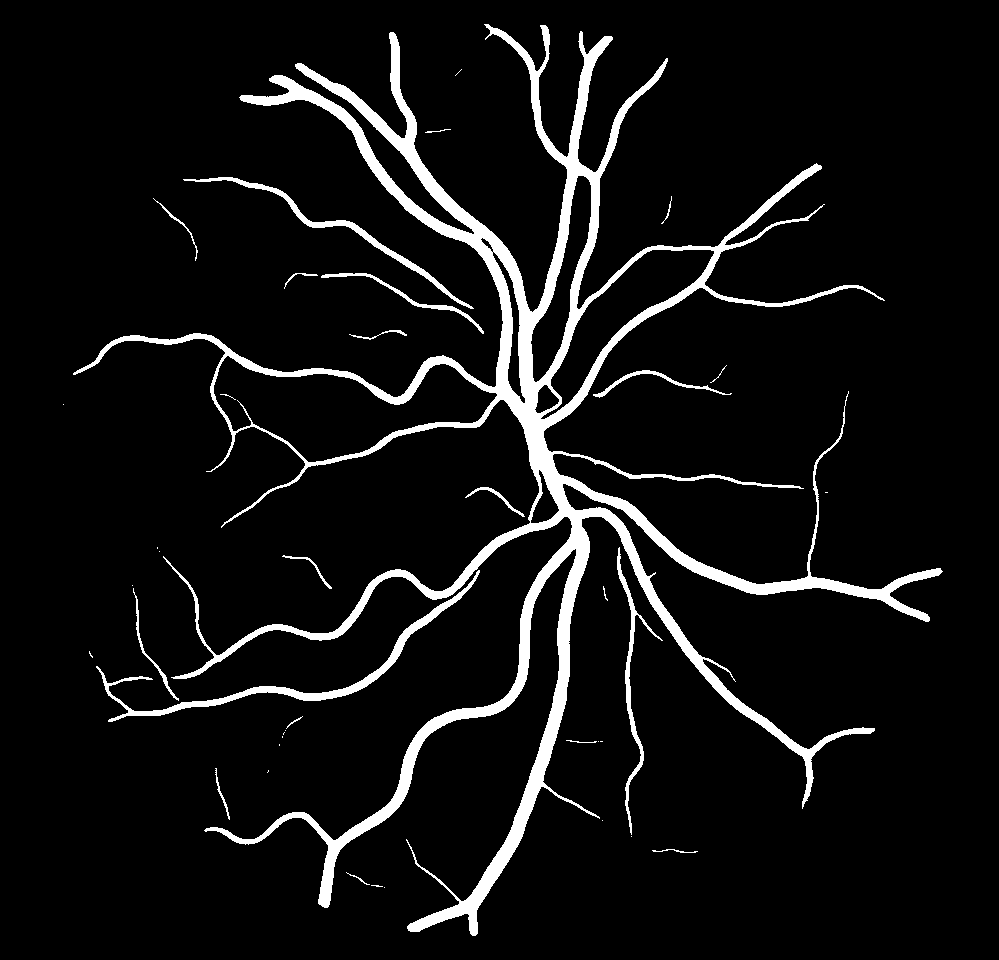

(a) Reference (b) Output (c) Width Map

IV-C Vessel Width Estimation

From the segmentation predicted by the SegRAVIR network, our model measures the diameter of the arteries and veins. To this end, the segmentation probability map is first thresholded, using a constant value of 0.5, to obtain the medial curves of the vessels by iteratively identifying and removing border pixels while maintaining vessel connectivity, in an approach similar to the thinning algorithm presented by Zhang et al. [49]. Then, the distance transform of the medial curve mask is multiplied with the segmentation mask in a pixel-wise manner. The result is the diameter distance map with respect to the medial curves of the segmented vessels.

VI-B Vessel Width Estimation

Table VI presents a quantitative comparison of the measured diameters using the segmentation outputs of SegRAVIR and competing approaches. Using the pixel-wise annotated masks, the reference average diameter of the arteries and veins in the test set of the RAVIR dataset were measured as and , respectively. According to our analysis, SegRAVIR can accurately measure the diameter of the vessels and it achieves the smallest MAPE among the competing approaches. Specifically, in comparison to CE-Net, Iter-Net, and DU-Net, respectively, SegRAVIR is on average , and more accurate in terms of MAPE for the measured diameter of arteries and , and in terms of MAPE for the measured diameter of veins. Fig. 6 presents qualitative comparisons of reference and SegRAVIR estimated diameter maps.

(a) (b) (c)